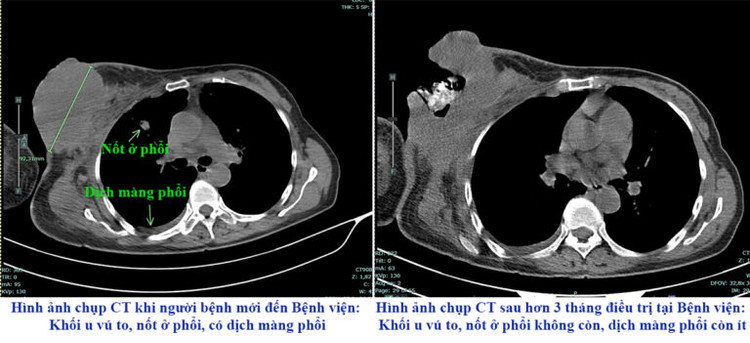

Tháng 8/2024, người bệnh đến Bệnh viện đa khoa tỉnh Phú Thọ trong tình trạng suy kiệt, khối u vú phải kích thước lớn, vỡ loét chảy dịch, thâm nhiễm rộng tổ chức da vùng ngực, di căn hạch và di căn xa nhiều nơi. Với trường hợp này điều trị và chăm sóc rất khó khăn.

| Hình ảnh chụp CT trước và sau điều trị của người bệnh - Ảnh BVCC |